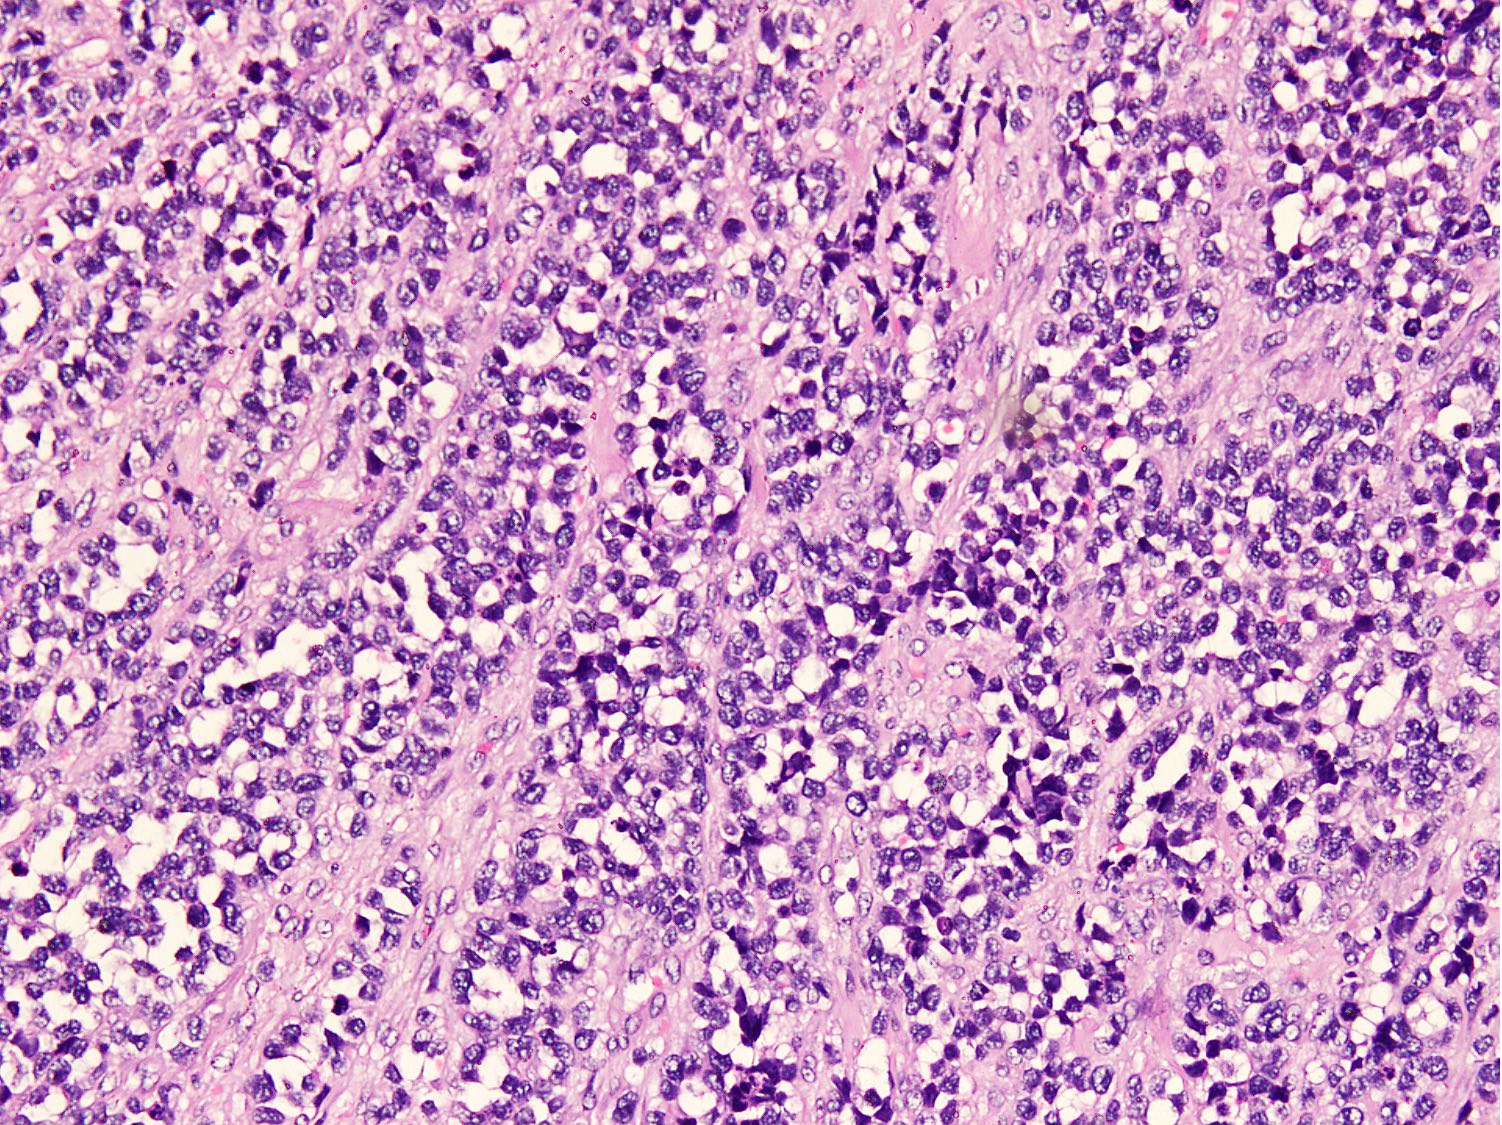

Microscopic (histologic) description

- Cellular round cell tumor

- Large clusters, nests, cords and trabeculae of primitive round cells, separated by variably thick fibrovascular septa

- Loss of cellular cohesion in the center forms alveolar-like, cystic and vague papillary appearance (Histopathology 2022;80:98)

- Layer of cells adheres to the periphery of the spaces and fibrous septa

- Small to intermediate sized monomorphic cells with scant cytoplasm

- Hyperchromatic nuclei with variable conspicuous small nucleoli

- Cells in the center have poor preservation and are necrotic; may appear floating

- Multinucleated tumor giant cells with wreath-like lineup of nuclei are common (Acta Pathol Microbiol Immunol Scand A 1982;90:345)

- Round to oval rhabdomyoblasts with abundant acidophilic cytoplasm may be present

- Brisk mitosis and variable tumor necrosis

- Solid variant:

- Sheets of neoplastic cells

- Lack fibrovascular septa, pseudoalveolar spaces and dyscohesion (Cancer Genet Cytogenet 2005;163:138)

- May show rhabdomyoblastic differentiation

- Abundant mitotic activity

Microscopic (histologic) images

Contributed by Nasir Ud Din, M.B.B.S.